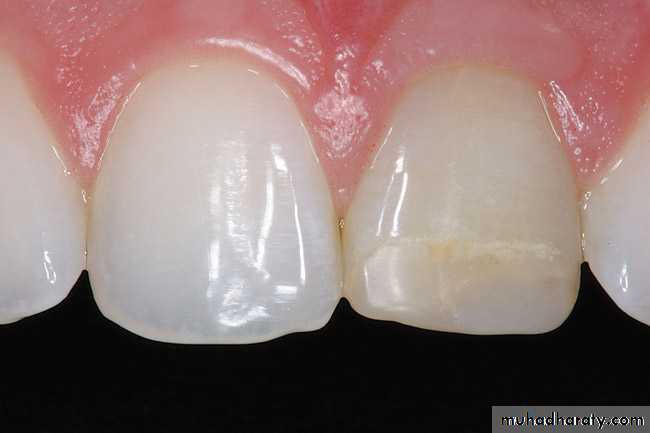

2. White Line Or Halo Around The Enamel Margin

Potential solutions include:

1. Re-etch, prime, and bond the area.2. Conservatively remove the fault and rerestore.

3. Use a traumatic finishing techniques (e.g., light intermittent pressure).

4. Use slow-start polymerization techniques.

5. Leave as is.